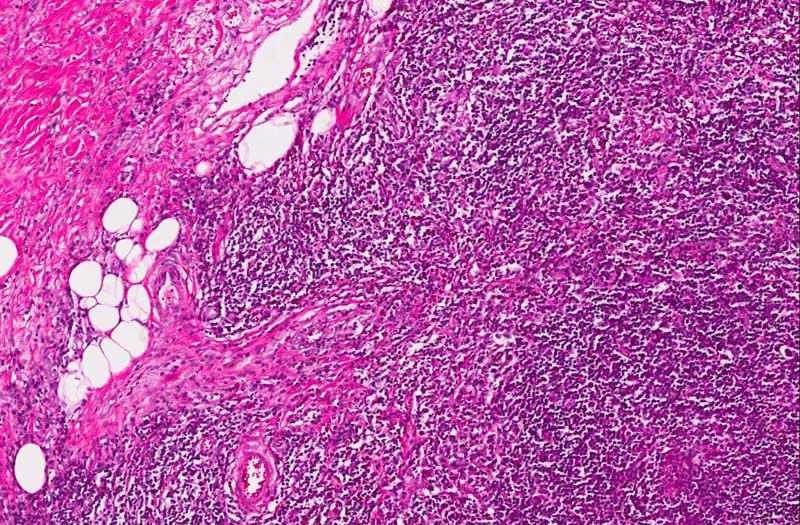

• This tumor has several notable features. It is composed predominantly of small lymphocytes without any suggestion of lymphoma. Among these lymphocytes are scattered large, atypical cells with one or, less commonly, multiple nuclei (area 1). Many of the nuclei are lobulated and typically a prominent, eosinophilic nucleoli are present. The distribution of these cells are not homogeneous. They are hard to find in some areas. Also present in this backgound of lymphocytes are eosinophils (area 2). Again, their distribution is also non-homogeneous. The background of this tumor is very fibrotic and many nodules (arrow) surrounded by the fibrous tissue is present. These features are classic for nodular sclerosing type of Hodgkin lymphoma. The large atypical cells in fact are subclassified into the several categories as discussed below. Many of them can be found in this case.

• In order to make a diagnosis of the nodular sclerosing type, there must be collagen bands that surround at least one nodules and lacunar type Reed-Sternberg cells.